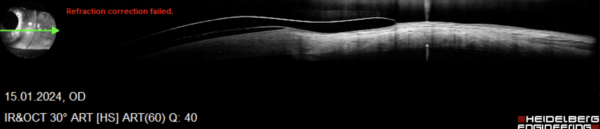

Anpassung einer Freiformsklerallinse bei einem Keratokonus Grad 2

Aufgrund der Unverträglichkeit von kleinen formstabilen Keratokonuskontaktlinsen erfolgte die Anpassung von Sklerallinsen in Freiform-Technologie. Wie auf den Schnittbildern des Vorderabschnitt-OCTs zu sehen ist, liegt der Randbereich harmonisch auf der Sklera bzw. Bindehaut auf. Daher können die Linsen täglich 15 Stunden getragen werden. Die Linsen wurden mit 72 peripheren Linsen-Rand-Sektoren für das Auge gefertigt.